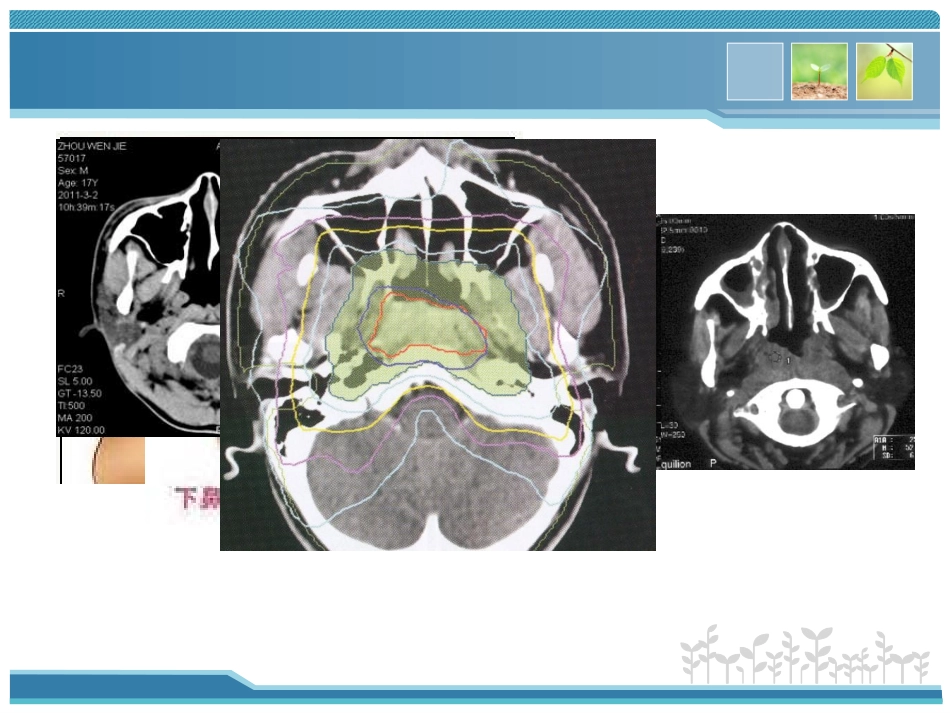

鼻咽癌放射治疗并发症及处理资料由PPT中国(1ppt)收集提供下载,版权归原作者所有放疗科方敏口腔粘膜反口腔粘膜反(oralmucositis,OM)(oralmucositis,OM)放射性皮肤损伤放射性口腔黏膜炎急性放射性腮腺炎口腔干燥、味觉减退张口困难放射性中耳炎远期并发症放射性皮肤损伤放射性口腔黏膜炎急性放射性腮腺炎口腔干燥、味觉减退张口困难放射性中耳炎远期并发症常见并发症常见并发症皮肤急性放射损伤分级标准(RGOT)慢性反应放疗后数月或数年出现的反应。表皮萎缩变薄,浅表毛细血管扩张,有色素沉着、脱屑,皮肤瘙痒,易破溃放射性皮炎预防注意保护放射野皮肤:不在放射野内贴胶布或胶膏,保护局部皮肤清洁、干燥,禁用肥皂清洗,亦不得使用其他刺激性化学品,如洗发剂、染发剂、碘酒、酒精等。避免对放射野的机械性刺激:如不随便抓搓,不穿硬领、硬质衣服;不用剃刀剃放射野皮肤。放射野在易受摩擦的部位如腋窝、会阴、胸部、腹股沟等处应注意减少摩擦。避免强烈的阳光直接暴晒,避免强风、过热、过冷等刺激,局部禁用暖具和冰袋。放疗部位禁做注射点。合理的饮食:放疗期间及结束后一段时间,应多吃富含维生素A、C的食物,如多食牛奶、鱼肝油、鸡蛋、新鲜蔬菜水果等。因为维生素A能改善皮肤细胞功能,维生素C能促进损伤皮肤的修复。放射性皮炎治疗•保持皮肤清洁干燥,避免感染•外涂皮肤保护剂、修复剂如:奥克喷、贝复剂•氦氖激光联合贝复剂治疗急性放射性口腔黏膜炎诊断分级标准轻度疼痛,口腔黏膜充血、红斑中度疼痛,能进食流质,片状黏膜炎炎性分泌物、水肿或溃疡重度疼痛、吞咽困难,纤维素性黏膜炎、水肿、溃疡重度疼痛、不能进食,黏膜溃疡、出血、坏死。Ⅰ度Ⅳ度Ⅲ度Ⅱ度口腔黏膜炎的处理预防保持口腔清洁对症处理消炎的喷剂口腔护理液漱口含麻醉剂的含漱液正确的漱口方法促进粘膜愈合的药物清热利咽生津的中草药鼻饲、静脉营养饮食指导禁忌粗硬烫及刺激性食物进温凉清淡易消化的半流质多食新鲜蔬菜水果补充维生素ABCE多饮水葆尔爽口腔护理液葆尔爽口腔护理液鼻咽癌患者放射治疗前局部冰敷减轻口腔黏膜反应的效果(龚光明倪杰中华护理杂志2019年8月第46卷第8期ChinJNurs,August2019,Vol46,No.8)结论:放射治疗前局部冰敷可有效预防与减轻鼻咽癌放射治疗所致口腔黏膜反应,减少口腔真菌感染放化疗后口腔黏膜炎的研究进展薛松霞现代口腔医学杂志2019年第24卷第4期JModernStomato,lJuly2019,Vol24,No.低剂量激光治疗(Low-levellasertherapy,LLLT)。LLLT可以减少高剂量化疗或造血干细胞移植前放化疗的患者OM的发生率4氦氖激光在预防口腔粘膜反应中的应用研究患者女诊断为右鼻咽低分化鳞癌,行IMRT放疗加顺铂同步化疗,现剂量达3000cGy,口腔粘膜糜烂,附片状伪膜,诉口腔疼痛影响进食,颈部放射野皮肤色素沉着,片状脱屑,张口轻度受限。医嘱予鼻腔冲洗,口腔护理液漱口、氦氖激光照射、欣洛维口服查血常规示白细胞2.76×109/L红细胞2.82×109/L血红蛋白94g/L患者出现了哪些放疗并发症?患者出现了哪些放疗并发症?